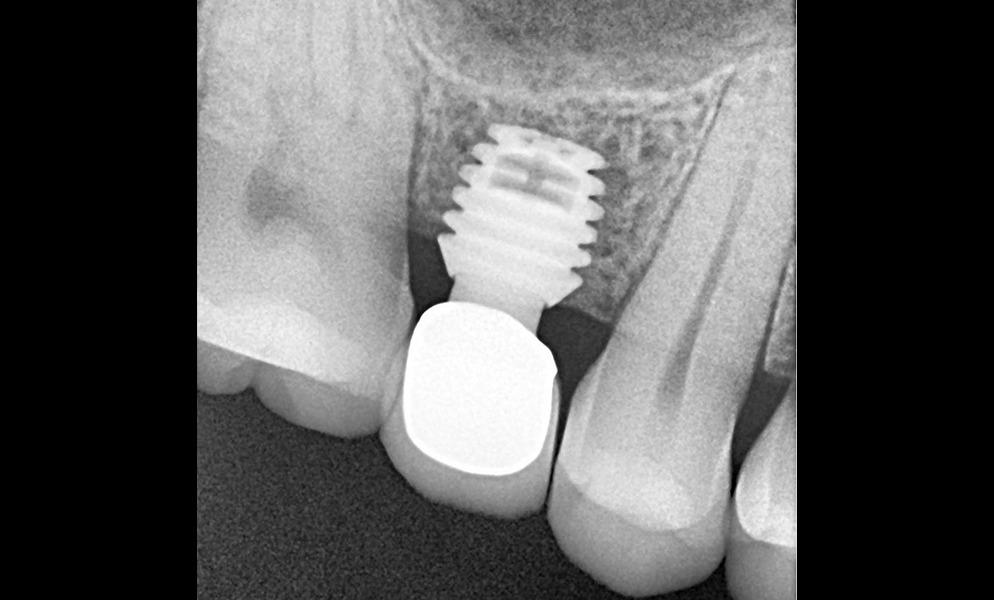

| Before | After |

![]() |

| Single posterior tooth missing space restored with a 5x5 mm short dental implant (Bicon, USA) to avoid sinus lift and bone graft procedures | |